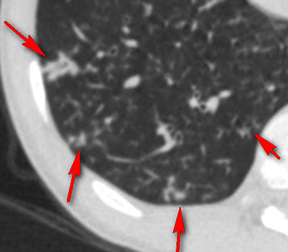

好在小夥肺功能雖然有阻塞,總體上沒有影響到生活,說話中氣很足,就是痰多,而且很難排出來,做了個胸部CT肺上面除了支氣管擴張之外,長了很多結節,就像一把“芝麻”撒在了肺上,有些芝麻恰巧撒在了擴張的終末細支氣管的旁邊,就像樹枝上發出的芽,所以稱為“樹芽徵”。

很多看過我科普的朋友應該知道是什麼疾病了,集齊了鼻竇炎、大量痰、呼吸阻塞、支氣管擴張、樹芽徵等這幾個要素的肺病,診斷就已經很明確了,那就是瀰漫性泛細支氣管炎,這個病首先由日本學者報道,需要長期使用大環內酯類藥物(比如紅黴素、阿奇黴素)治療,這個病如果不認識他,很有可能被長期誤診為慢性支氣管炎或者慢性阻塞性肺病,如果認識了他就好診斷了,早期診斷沒有形成支氣管擴張的話,口服阿奇黴素效果很好,甚至能治癒。